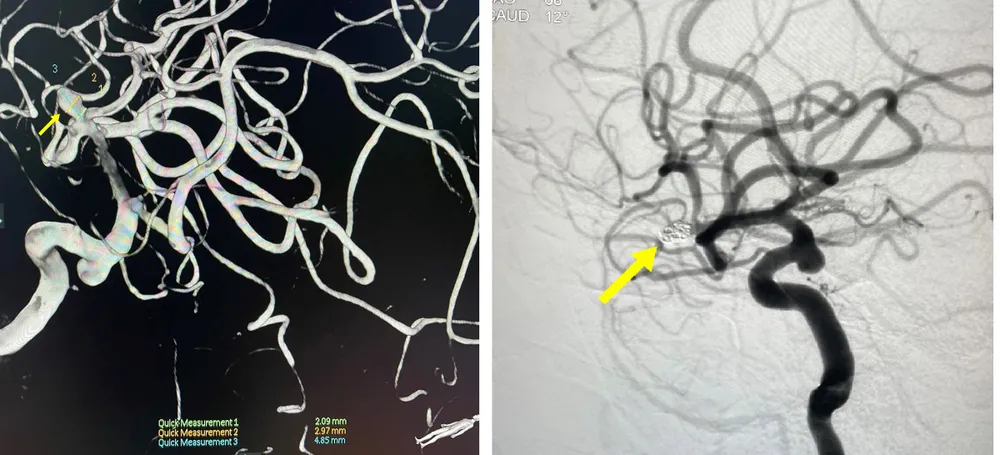

Túi phình động mạch não giữa trước (bên trái) và sau khi được tắt bằng cuộn kim loại. Ảnh: BVCC